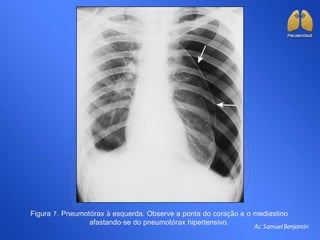

Figura 7. Pneumotórax à esquerda. Observe a ponta do coração e o mediastino

afastando-se do pneumotórax hipertensivo.

Figura 7. Pneumotóraxà esquerda. Observe a ponta do coração e o mediastino afastando-se do pneumotórax hipertensivo.